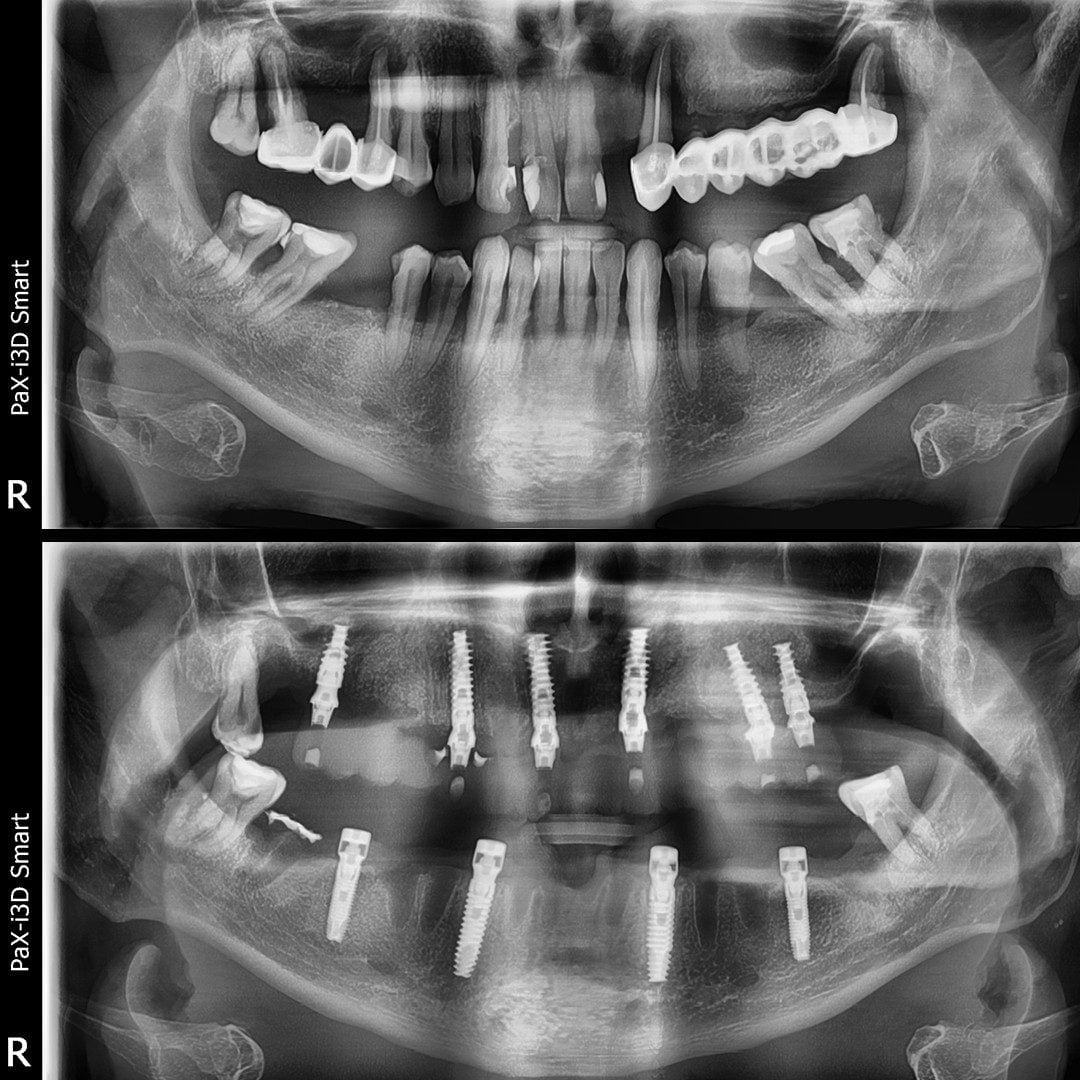

- Intervenția chirurgicală

- Aplicare lucrare provizorie pe implanturi

Peste 4000 Implanturi dentare inserate

tehnica All-on-4/All-on-6